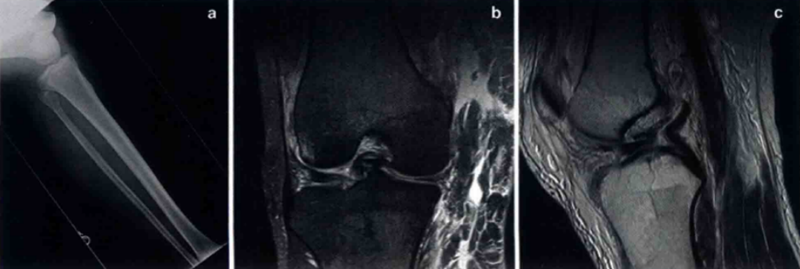

在全面体格检查后,应进行正、侧位X线检查证实,以诊断骨折和评估股骨、胫骨的移位。术后X线可用于评估复位后关节力线是否恢复。MRI在鉴定损伤结构、程度和部位上十分有用。在膝关节脱位和/或多发性创伤时使用CT血管造影术来确保血管无损伤。

图 a.膝关节脱位X线片;b.膝关节脱位的MRI冠状位;c.矢状位MRI